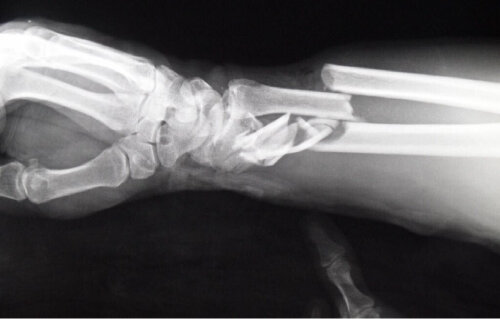

После хождения по травмпунктам и хирургам, после дополнительных снимков точный диагноз маме так и не поставили. Почему все-таки болит плечо непонятно. То ли это последствия травмы, то ли обострился артроз…

Хирург в поликлинике не смог разобраться, и даже по результатам контрольных снимков не смог дать каких-то понятных комментариев. Но назначил физиотерапию и уколы.